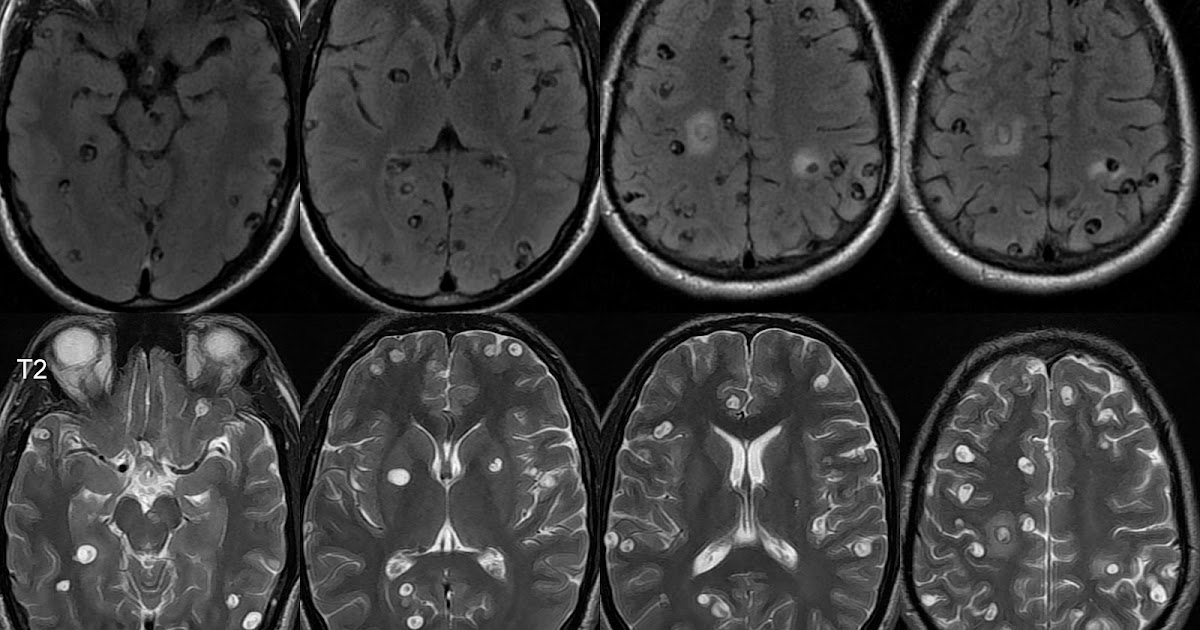

Нейроцистицеркоз и эхинококкоз что это такое - фото презентация